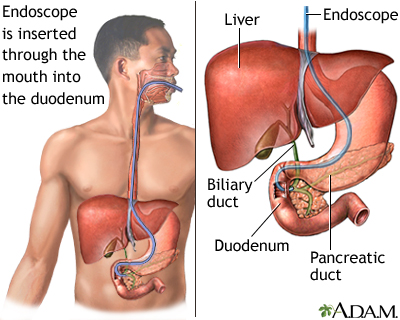

- Besides the gallbladder, gallstones may also be present in the common bile duct. Endoscopic retrograde cholangiopancreatography (ECRP) with endoscopic sphincterotomy is the most common procedure for detecting and managing bile duct stones. It may be performed before, during, or after gallbladder removal.

Endoscopic Retrograde Cholangiopancreatography (ERCP)

Endoscopic retrograde cholangiopancreatography (ERCP) was once the gold standard for detecting common bile duct stones, particularly because stones can be removed during the procedure. (SeeSurgery

below for details on the procedure.)However, this technique is invasive and carries a risk for complications, including pancreatitis. With the technological advancement of noninvasive imaging techniques, ERCP is now generally limited to patients who have severe cholangitis and a high likelihood of common bile ducts stones, which would need to be removed. It may also be used to diagnose biliary dyskinesia.

- Endoscopic retrograde cholangiopancreatography (ERCP) with endoscopic sphincterotomy (ES) is now the most frequently used procedure for detecting and treating common bile duct stones. The procedure involves the use of an endoscope (a flexible tube containing a miniature camera and other instruments), which is passed down the throat to the bile duct entrance.

The ERCP and ES Procedure

A typical ERCP and endoscopic sphincterotomy (ES) procedure includes the following steps:

- The patient is given a sedative and asked to lie on their left side.

- An endoscope (a tube containing fiber optics connected to a camera) is passed through the mouth and stomach and into the duodenum (top part of the small intestine) until it reaches the point where the common bile duct enters. This does not interfere with breathing, but the patient may have a sensation of bloating.

- A thin catheter (tube) is then passed through the endoscope.

- Contrast material (a dye) is injected through the catheter into the opening of the duct. The dye allows x-ray visualization of the biliary tree (the system of ducts through which bile flows, including the common bile duct) and any stones contained in the area.

- Instruments may also be passed through the endoscope to remove any stones that are detected.

- The next phase of the procedure is known as endoscopic sphincterotomy (ES). It is also sometimes referred to as papillotomy, although this is a slightly different variation. ES widens the junction between the common bile duct and intestine (the ampulla of Vater) so that the stones can be extracted more easily. With ES, a tiny incision is usually made in the opening of the common bile duct and through the muscles that enclose the lower common bile duct (the sphincter of Oddi).

- One recent alternative to ES is the use of a small inflatable balloon (a procedure known as endoscopic balloon dilation) that opens up the ampulla of Vater to allow stones to pass. This variation does not involve cutting muscles, and offers a lower risk of bleeding and injury to internal structures. However, this carries a higher risk for pancreatitis.

- Once the junction has been opened, the stones may pass on their own, or they may be extracted with the use of tiny balloons, or sometimes baskets.

- During ERCP, a choledochoscope can be used to directly access the bile duct through the ERCP scope to visualize and potentially disrupt and/or remove stones (Spyglass is a disposable system that has been designed for this use).

Complications

Complications of ERCP and ES occur in 5% to 8% of cases, and some can be serious. Mortality rates are 0.2% to 0.5%. Complications include the following:

- Pancreatitis (inflammation of the pancreas) occurs in 3% to 9% of cases and can be very serious. Younger adults are at higher risk than older people. The risk is also higher with more complex procedures.

- Postoperative infection. Antibiotics may be given before the procedure to prevent infection, although one study reported that they had little benefit.

- Bleeding occurs in 2% of cases. There is an increased risk for bleeding in patients taking anti-clotting drugs, and those who have cholangitis. This complication is treated by flushing the area with epinephrine.

- Perforations (rare).

- Long-term complications include stone recurrence and abscesses.

- Larger bile duct stones (10 to 15 mm) are more difficult to remove and often require additional procedures.

ERCP and ES are difficult procedures, and patients must be certain that their doctor and medical center are experienced. ERCP can usually be performed successfully by an experienced doctor, even in critically ill patients who are on mechanical ventilators.

ERCP and Gallbladder Removal (Cholecystectomy). ERCP may be performed before, during, or after gallbladder removal. ERCP is often performed after gallstones in the common duct are discovered during cholecystectomy.

In some cases, stones in the gallbladder are detected during ERCP. In such cases, laparoscopic cholecystectomy is usually warranted. There is some debate about whether the gallbladder should be removed at the same time as ERCP, or if patients should wait.